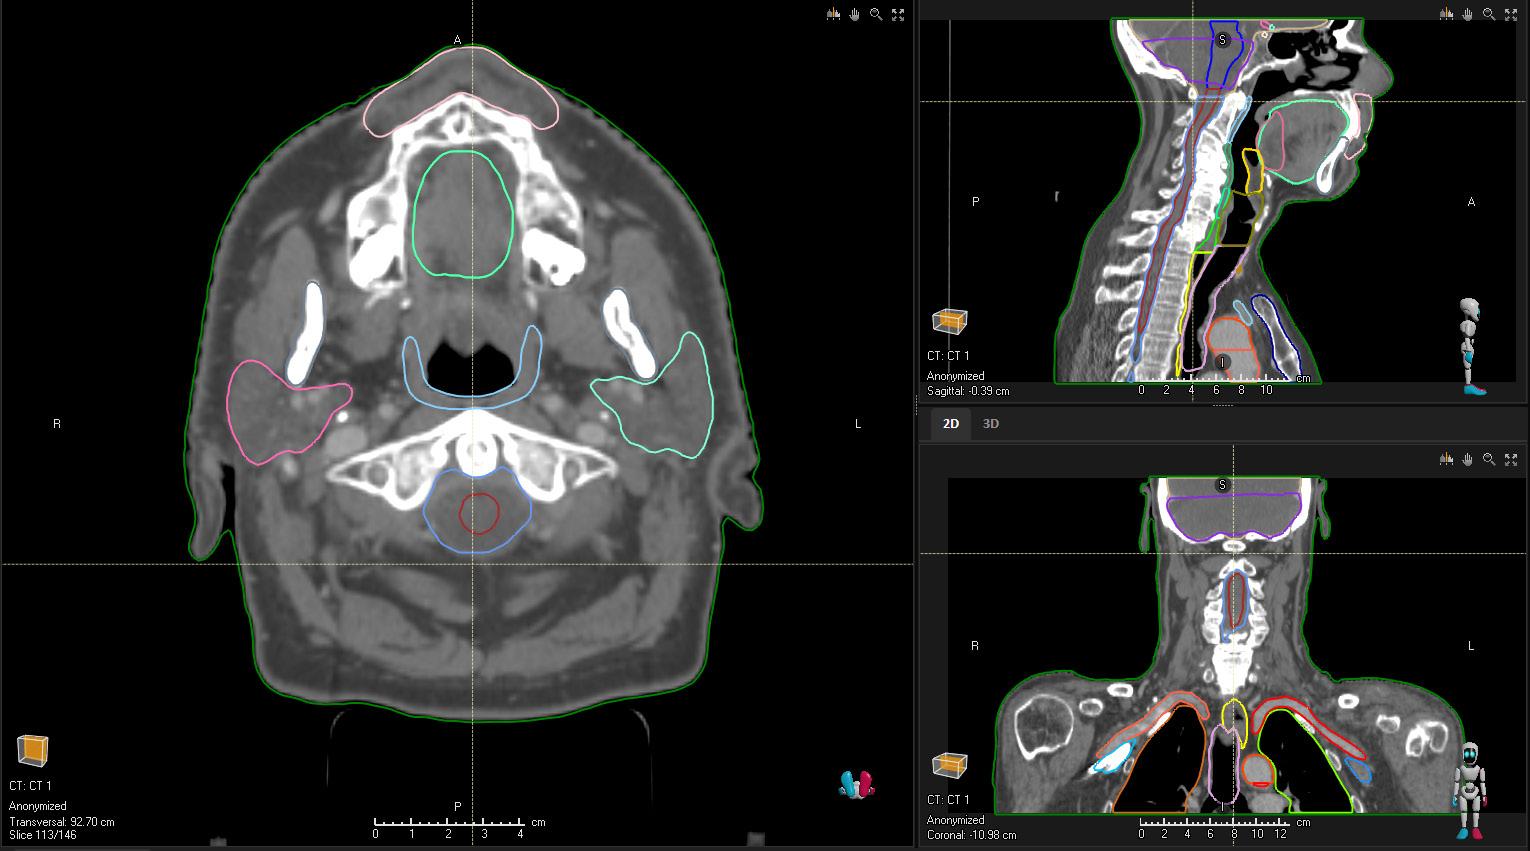

HEAD AND NECK (OAR) CT

STRUCTURES

Bone_Mandible Larynx_SG IMPROVED

Brain Lens_L

Brainstem Lens_R

Cavity_Oral Lips

Cochlea_L Musc_Constrict_I

Cochlea_R Musc_Constrict_M

Cricopharyngeus

Eye_L

Musc_Constrict_S

Nasolacrimal_Duct_L

Eye_R Nasolacrimal_Duct_R

Fossa_Posterior OpticChiasm

Glnd_Lacrimal_L OpticNrv_L

Glnd_Lacrimal_R OpticNrv_R

Glnd_Submand_L Parotid_L

Glnd_Submand_R Parotid_R

Glottis IMPROVED Pituitary

Joint_TM_L SpinalCord

Joint_TM_R Tongue_Base